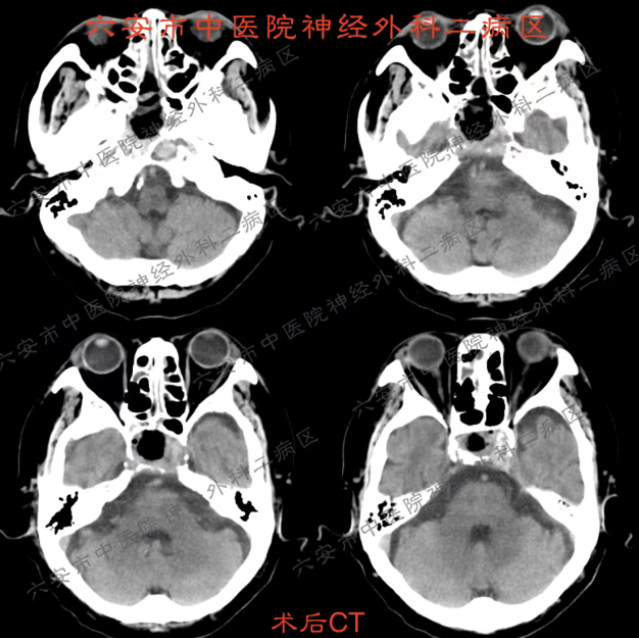

手术中,在内镜的清晰视野下,病变组织被精准切除,周围的视神经、重要血管保护完好。术后,章大爷没有出现任何并发症,恢复非常顺利。头痛消失了,视力、感觉、活动一切正常。住院观察几天后,各项指标平稳,他满意地办理了出院。